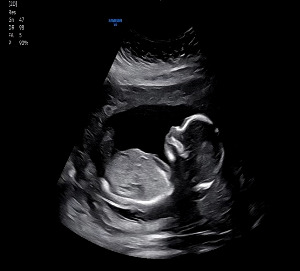

화면에는 이제 제법 사람 모습을 닮은 찹쌀이가 또렷하게 비쳤다.

손가락 다섯 개. 발가락 다섯 개.

팔, 다리 길이 균형, 장기 위치, 심장 네 방 구조까지

모두 이상 없음.

마지막으로 목투명대(NT)를 확인했다.

수치는 평균값 2.59mm.

검사를 진행하던 선생님은 고개를 끄덕이며 말했다.

“목투명대는 평균 범위입니다. 걱정하지 않으셔도 돼요.”

KakaoTalk_20250831_213642428_01.jpg 13주 차 1차 정밀 초음파